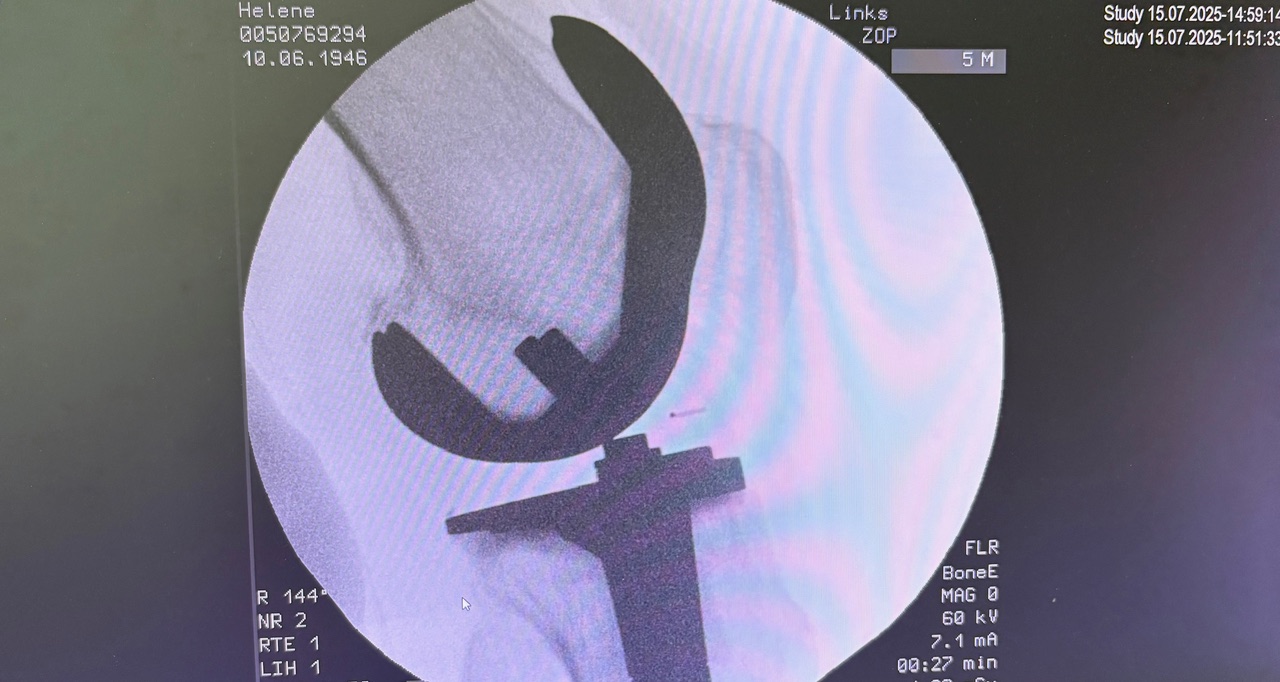

Η ρομποτική αρθροπλαστική γόνατος είναι προηγμένη τεχνική αντικατάστασης γόνατος, όπου ο χειρουργός χρησιμοποιεί ρομποτικό σύστημα υποβοήθησης για εξαιρετικά ακριβή τοποθέτηση των εμφυτευμάτων, βασισμένη στη δική σου ανατομία.

- Προεγχειρητικός σχεδιασμός με CT (συνήθως) → 3D μοντέλο γόνατος

- Καθορισμός ακριβών ορίων κοπών και ευθυγράμμισης

- Κατά τη διάρκεια του χειρουργείου:

- ο χειρουργός καθοδηγεί το ρομπότ

- το σύστημα δεν επιτρέπει αποκλίσεις από το σχέδιο

- Το εμφύτευμα τοποθετείται με χιλιοστομετρική ακρίβεια

Το ρομπότ δεν χειρουργεί μόνο του· λειτουργεί ως «έξυπνο εργαλείο» στα χέρια του ορθοπαιδικού.